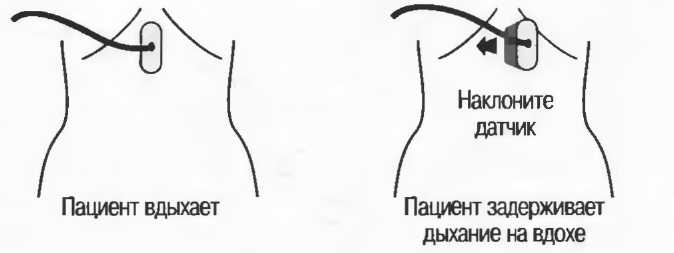

При поперечном сканировании изображение на экране монитора может перевернуться таким образом, что левая сторона пациента окажется с правой стороны экрана. Несмотря на то что на датчике имеется индикатор положения, важно перед исследованием визуально проверить соответствие стороны датчика соответствующей стороне получаемого изображения. Лучше всего это сделать, поместив палец на один конец датчика и посмотрев, с какой стороны экрана получится его изображение. При неправильной ориентации нужно развернуть датчик на 180" и проверить снова (рис. 8а). На продольных срезах голова пациента должна определяться на экране слева, а ноги—справа.

Газ отражает ультразвук и экранирует ткани, расположенные сзади, в результате преломления и акустической тени от газа. Газ в кишечнике может экранировать печень, поджелудочную железу, парааортальные лимфоузлы, матку, яичники. Иногда удается сместить газ в кишечнике, например при наличии наполнения мочевого пузыря матка и яичники почти всегда легко визуализируются, так как кишечные петли «убраны» из поля зрения. В других случаях бывает необходимо делать косые, латеральные или дорсальные сканы в положении пациента стоя или сидя (рис. 19).

|

Рис. 19. На эхограмме, полученной во время вдоха (слева), желчный пузырь визуализируется целиком, во время выдоха (справа) более чем половина желчного пузыря экранирована кишечным газом. |

Возможные положения пациента при экранировании тканей кишечным газом |